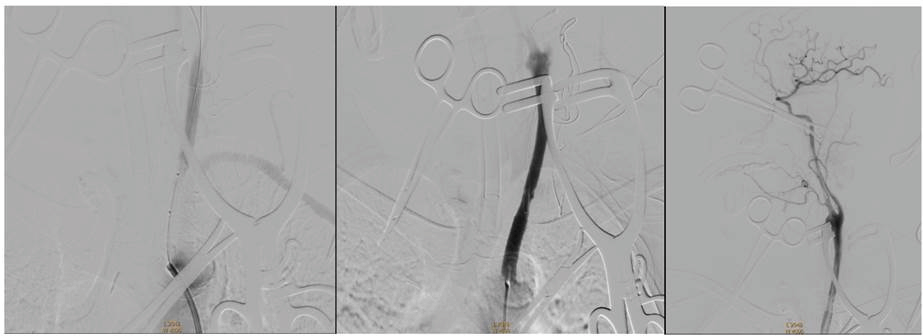

手术如期进行。在麻醉团队以及护理团队通力配合下,史怀璋主任,郑秉杰副主任首先为患者行左侧颈动脉内膜剥脱手术,术中手术顺利,剥脱后给予全脑血管造影检查,显示颈总动脉远端显影良好,但近端依然闭塞。随后,史怀璋主任及季智勇副主任通过微导丝通过闭塞处,成功释放一枚支架,最终成功完成了手术。术后患者无神经功能缺失,将于近日康复出院。